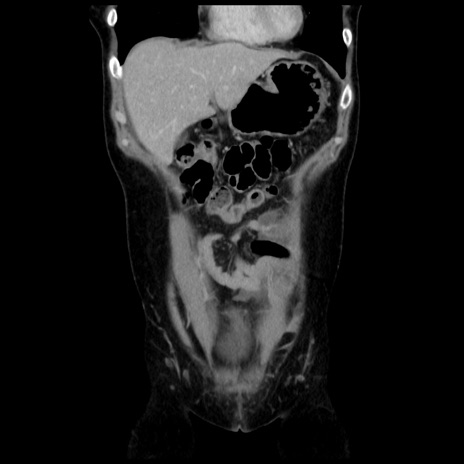

症例10(冠状断像)

【症例】 50歳代女性

【主訴】 腹痛

【現病歴】前日生レバーを食べた。今朝に排便あり。 昼前に突然発症の腹痛を生じ、当院救急外来を受診した。

【既往歴】 子宮筋腫にてで子宮全摘後

【身体所見】 意識清明、腹部:平坦、軟、下腹部やや左を中心に圧痛・反跳痛あり、筋性防御あり

【データ】WBC 7800、CRP 0.07